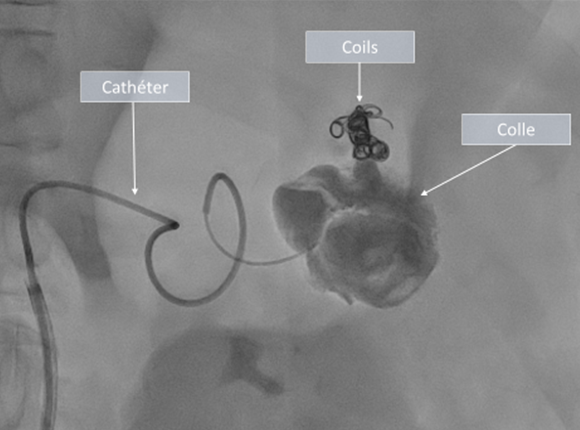

Le radiologue procède ensuite à l’embolisation par injection d’agents destinés à occlure les vaisseaux. Les agents utilisés diffèrent selon la lésion et la configuration anatomique des vaisseaux (spires, plugs, colle, …). Dans certains cas particuliers, le radiologue peut être amené à positionner un « ressort » (stent) permettant d’exclure l’anévrisme tout en préservant la bonne perméabilité de l’artère qui le porte.